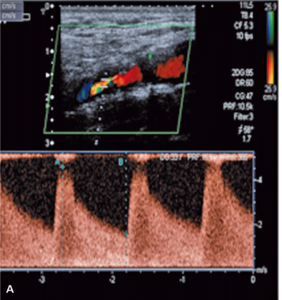

Standardem diagnostycznym dla tętnic dogłowowych są: ultrasonograficzne badanie doppler duplex tętnic szyjnych i kręgowych (klasa zaleceń I/A), angiografia metodą tomografii komputerowej lub rezonansu magnetycznego (klasa zaleceń I/A) [13]. Czułość i swoistość tych metod diagnostycznych w poprawnym rozpoznaniu stopnia ICAS sięga 95-100% w akredytowanych, certyfikowanych ośrodkach.

Badanie ultrasonograficzne doppler duplex tętnic szyjnych i ocena koła Willisa

Badaniem ultrasonograficznym można uwidocznić zwężenie i ocenić jego morfologię.